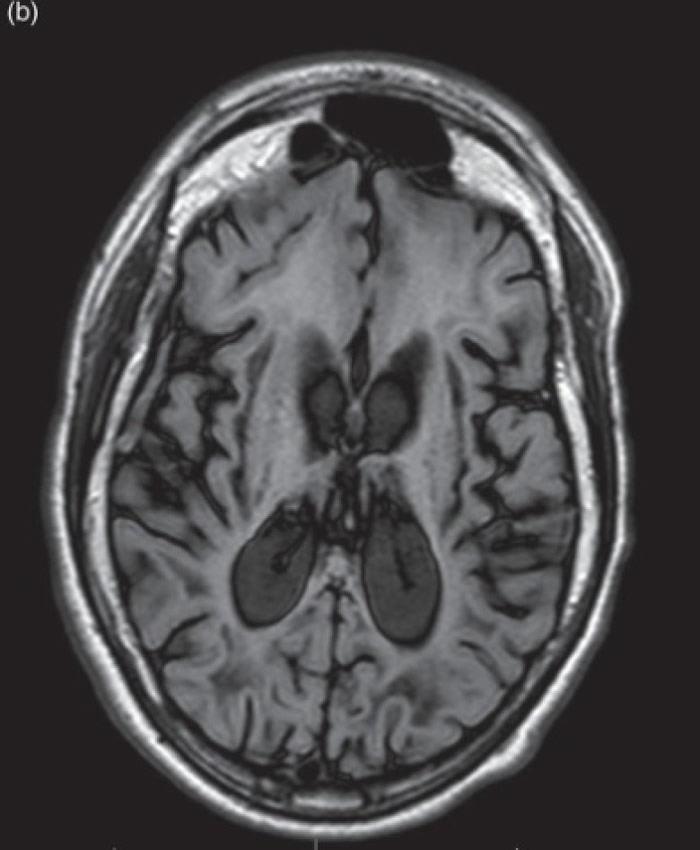

肾上腺脑白质退化症患者的脑部影像。